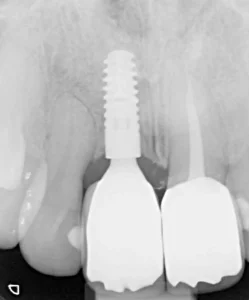

This lady was very upset after a dumbbell hit her mouth in the gym and knocked the front tooth out.

A temporary bridge was made to avoid her having to wear a temporary denture during the teatment, which is less comfortable.

A single implant with bone grafting was placed.

Once the implant was bedded into the bone, a new porcelain crown was fitted on the implant, and a new crown was placed on the adjacent tooth to match in better.